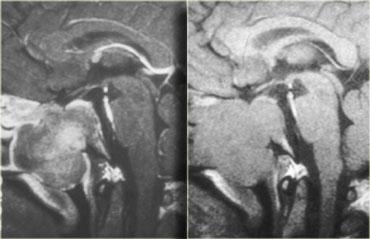

Trên các hình ảnh chuỗi xung T1W mặt phẳng đứng dọc không và có tiêm thuốc tương phản từ, có thể nhận thấy tuyến yên bị chèn ép.

Có một khối lớn trong hố yên và trên hố yên với các thành phần dạng nang, thành phần ngấm thuốc cũng như vôi hóa.

Các dấu hiệu này ở trẻ em gần như là đặc trưng bệnh lý của sọ hầu u (có thể chỉ cần chẩn đoán phân biệt với u bì – dermoid).

Hình ảnh mặt phẳng đứng ngang (coronal) của cùng một khối.